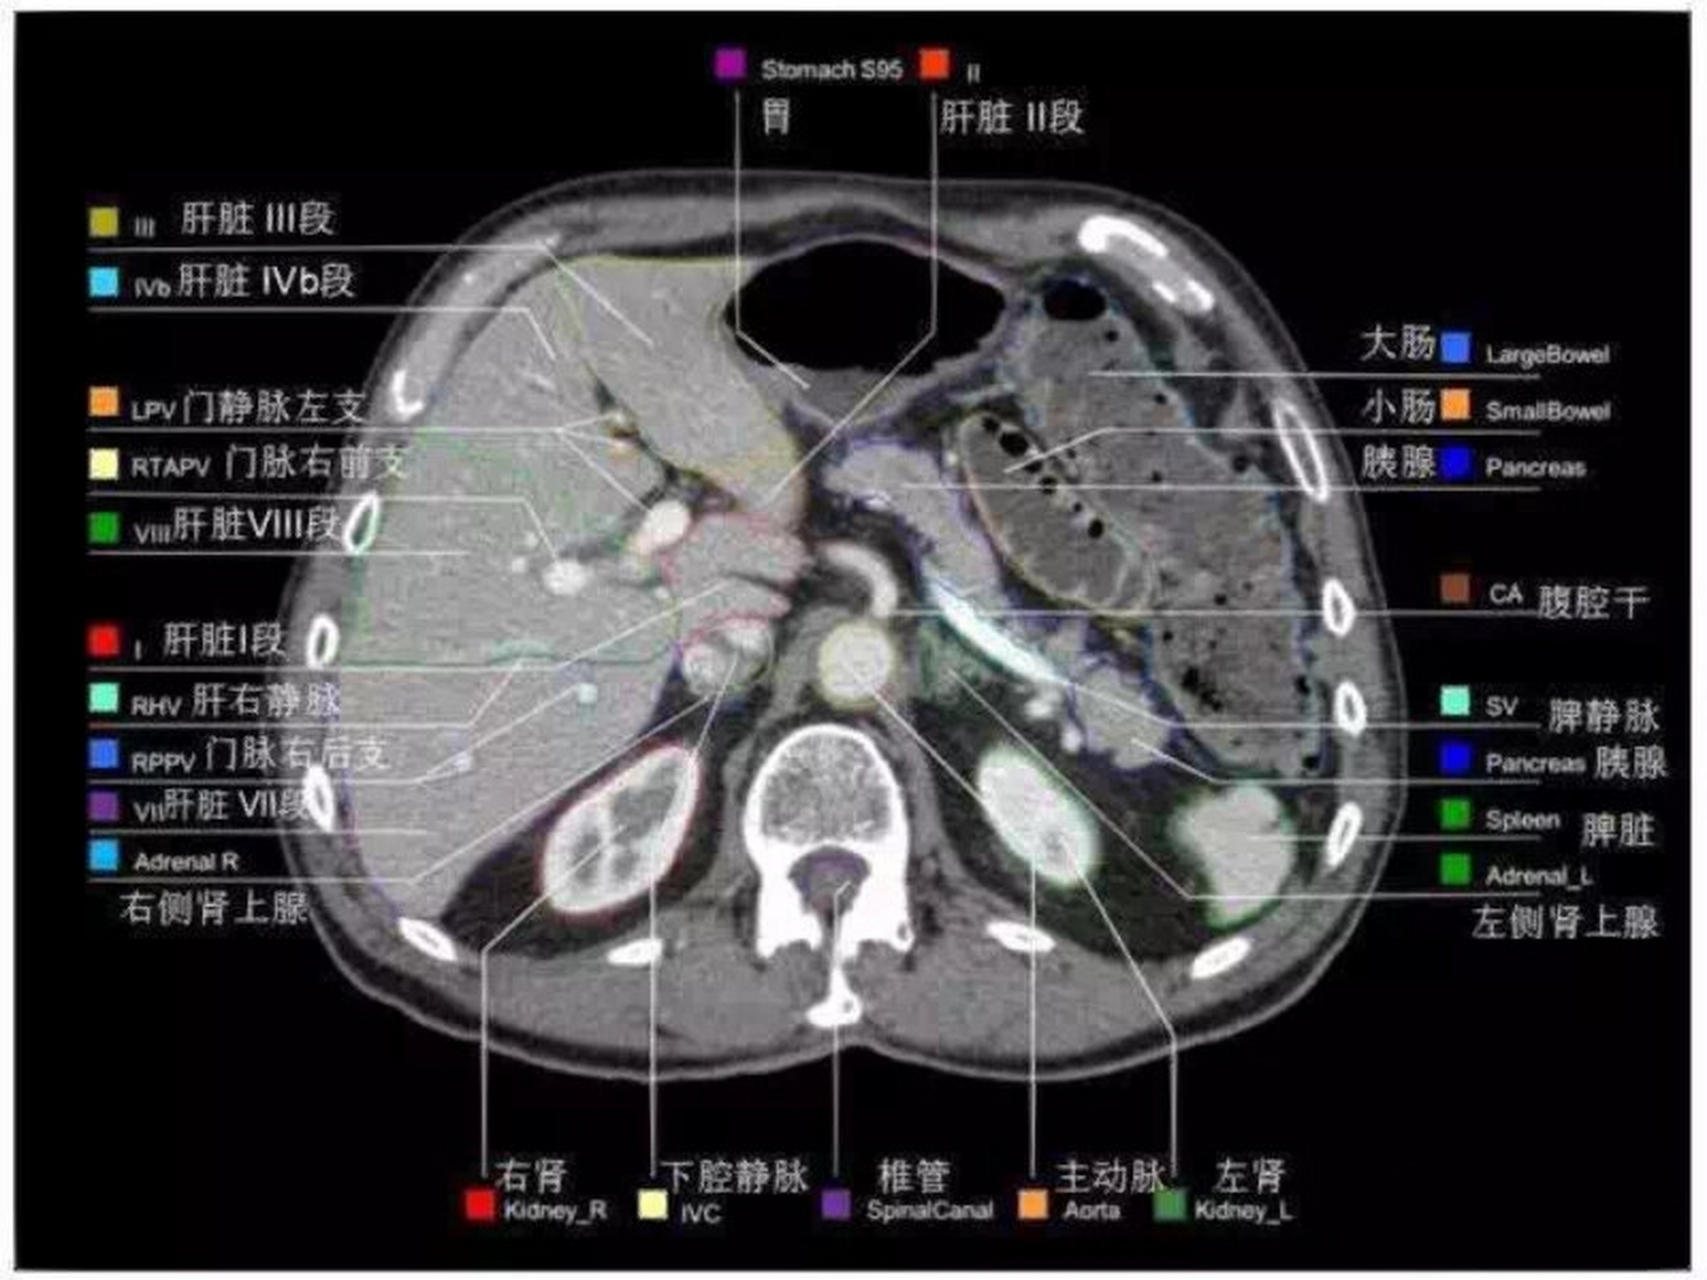

肝脏ct增强解剖!上腹部

图片尺寸1280x1706